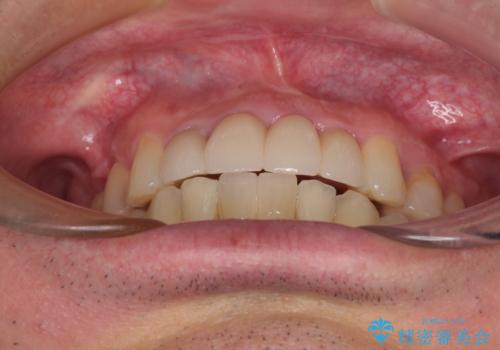

放置した歯列 矯正治療とインプラント治療で劇的に改善

矯正治療を行いながら、欠損部はインプラントによる補綴治療を希望されたため、補助装置を用いたワイヤー矯正によりスペースを確保しながら歯列を整え、適宜インプラントを埋入していくこととしました。

上顎前歯もインプラントを希望していらっしゃいましたが、両隣の歯根が近接しており、インプラントは困難と判断したためオールセラミックブリッジによる補綴治療を前提として治療を開始することとしました。

下顎前歯にインプラントを2本埋入するのは非常に困難であり、どうしても歯肉位置に土台の金属色が見えてしまう仕上がりとなりました。無理をせずに1本のみの埋入とするか、ブリッジを提案しましたが、患者様の強い希望により、2本埋入することとなり、大変満足していただけました。